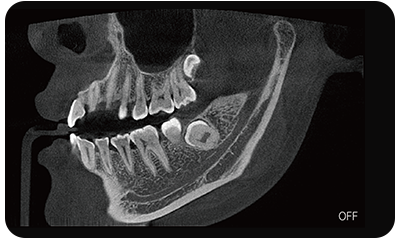

超能去伪 至臻影像

局部超清显示、 移动视野摄片

真人正侧位投影,实现CT成像区域无极可调

可根据临床需求任意调整成像区域大小实现局部超清三维显示

可根据临床需求任意调整成像区域大小实现局部超清三维显示

临床样片